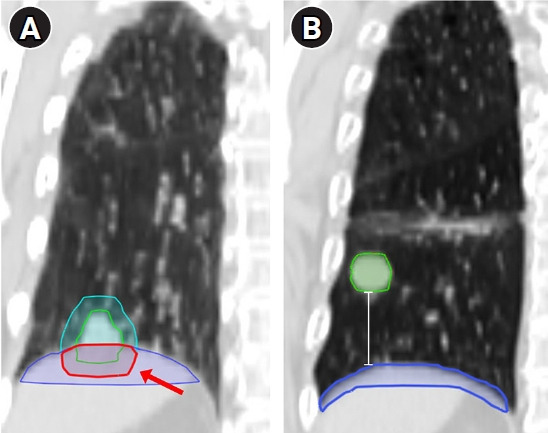

Results: Thirty-two patients with 39 tumors were analyzed, after the withdrawal of five patients due to discomfort. For 26 tumors separated from the diaphragm, CPAP significantly increased the superoinferior distance between the tumor and the diaphragm (5.96 cm vs. 8.06 cm; p < 0.001). For 13 tumors located adjacent to the diaphragm, CPAP decreased the overlap of planning target volume (PTV) with the diaphragm significantly (6.32 cm3 vs. 4.09 cm3; p = 0.002). PTV showed a significant reduction with CPAP (25.06 cm3 vs. 22.52 cm3, p = 0.017). In dosimetric analyses, CPAP expanded lung volume by 58.4% with a significant reduction in mean dose and V5 to V40. No more than grade 2 adverse events were reported.

Conclusion: This trial demonstrated significant improvement of CPAP in target delineation uncertainties for lung SABR, with dosimetric benefits, a favorable safety profile and tolerability. Further investigation is warranted to explore the role of CPAP as a novel strategy for respiratory motion management.